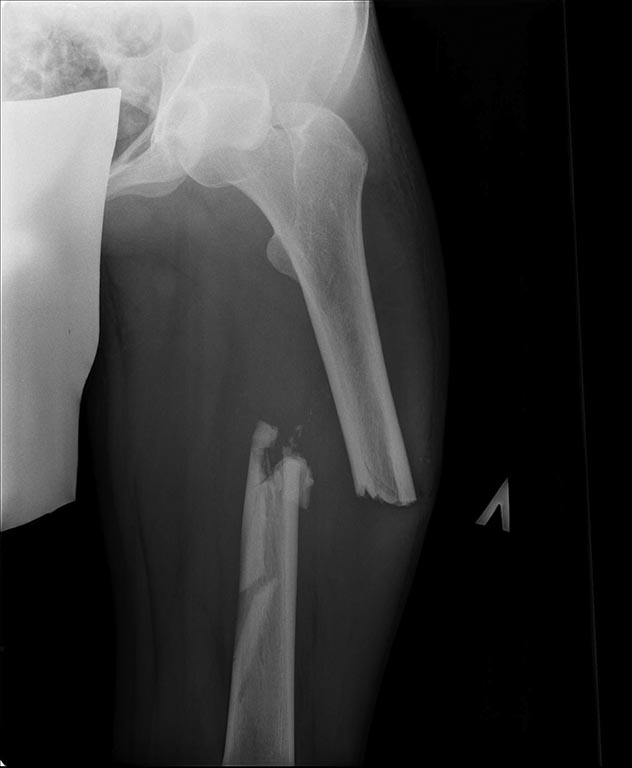

Добрый день уважаемые коллеги. Вашему вниманию представляю пациента(мужчина, 30 лет). Тяжелая сочетанная травма 7 мес. назад. Из скелетной травмы: открытый перелом бедра, открытый перелом дистального метаэпифиза левого плеча, закрытый перелом шейки левого плеча). Все повреждения были прооперированы. Бедро синтезировано штифтом Остеомед d-11мм. Раны зажили первично. Пациент после выписки впервые появился на контрольный осмотр ч/з 7 месяцев. Жалобы на боли в левом бедре при нагрузке, ощущение подвижности в месте перелома. Передвигается без дополнительных средств опоры. Локально: отека левого бедра нет, п/операционные рубцы без признаков воспаления. движения в суставах левой н/конечности в полном объеме, безболезненны.( все снимки, первичные, после операции и на сегодня прилагаю). основной вопрос, тактический, чем лучше выполнить реостеостеосинтез. У нас в наличии имеется: из штифтов Остеомед d-12мм, старый набор Синтез с канюлированными штифтами максимальный d-14мм., пластины LC-DCP, аппарат Илизарова. В плане 2 варианта: 1) удаление проксимальных блокирующих винтов(сломаный тоже), фиксация бедра спице-стержневым аппаратом из 2-х опор и компрессия в аппарате. 2)удаление металлоконструкции, и выполнение реостеосинтеза с рассверливанием( учитывая очень широкий канал) с установкой винтов поллеров в дистальном отломке. Жду ваших предложений и мнений. Спасибо заранее

С возросшей регулярностью на форуме обсуждаются «беспричинные» случаи несращения переломов после интерлокинга. В постах больше внимания уделяется обсуждению тактике дальнейшего лечения. Причём в подобных случаях предлагаемые варианты не отличаются многообразием и ограничиваются либо таким же остеосинтезом только стержнем большего диаметра, либо пластинкой с костной пластикой либо внеочаговой фиксацией. К сожалению, почти всегда остаются без анализа возможные причины, приведшие к несращению. А жаль. Ведь вероятность сращения после интерлокинга приближается к ста процентам, и точно установленная причина, почему это не произошло в положенные сроки, может подсказать тактику дальнейшего лечения. С моей точки зрения, безусловной причиной несращения перелома бедренной кости в обсуждаемой случае является оставшаяся подвижность между проксимальным и дистальными фрагментами после остеосинтеза. На это указывает и сам больной. Причём очаг нестабильности расположен в проксимальном костном фрагменте между ним и проксимальным концом стержня. Хотя на первый взгляд кажется, что вся проблема в дистальном костном отломке, точнее в отсутствии стабильности между ним и дистальным концом стержня из-за значительной разницы в диаметрах стержня и костномозгового канала. На последних рентгенограммах чётко видна костная мозоль между латеральным кортикальным слоем и стержнем на входе в костномозговой канал дистального отломка. Она говорит об эффективности дистального блокирования тремя блокирующими винтами в полифокальных плоскостях. И на сегодня биомеханическая система дистальный отломок – стержень работает как единое целое. Формируется новый костномозговой канал в дистальном отломке по ходу дистального конца стержня за счёт образования костной мозоли между латеральным кортикальным слоем и стержнем. И этот формирующийся костномозговой канал точно соответствует диаметру стержня, что является дополнительным фактором, стабилизирующим дистальный конец стержня. Поэтому, с моей точки зрения, не имеют смысла предложения, направленные на введение каких-либо металлоконструкций, уменьшающих размер костномозгового канала дистального отломка. Да и сделать это технически при такой рентгенологической картине крайне сложно, если вообще возможно. Что касается проксимального блокирования. Крайне неудачно проведен самый проксимальный блокирующий винт. Если авторы рассчитывали на последующую динамизацию (что, при таком переломе крайне неразумно), то его надо было проводить по верхнему краю овального отверстия. Если предполагалось статическая фиксация на протяжении всего периода сращения, то было бы разумнее его провести по нижнему краю овального отверстия. Тогда нагрузка при передвижении больного распределялась бы на оба проксимальных блокирующих винта, что снизило бы вероятность их перелома. Я уже писал в предыдущих постах с похожими случаями. Два блокирующих винта во фронтальной плоскости, один из которых проведен через овальное отверстие, не могут обеспечить стабильность во фронтальной плоскости, если костномозговой канал на выходе из проксимального отломка не соответствует диаметру стержня. И это, с моей точки зрения, служит наиболее частой причиной несращения. И это же служило причиной частых несращений при фиксации тонкими стержнями без рассверливания костномозгового канала. В данном случае мы бы рассверлили канал до диаметра канала на выходе из проксимального отломка (13-14 мм) и имплантировали бы стержень такого же диаметра как последнее сверло. Отдаю предпочтение протезированию всей длины бедренной кости с дистальным блокирование в мыщелках. Лучший вариант, с моей точки зрения, – реконструктивный стержень с проксимальным блокированием в шейке бедра двумя винтами. Хотя допустим и обычный стержень с расположением винта в овальном отверстии по его нижнему краю. Режим фиксации, безусловно, статический.

Непохоже. Вверху он нормально держался, и внизу центрального отломка канал неширокий. Подвижность явно была, но скорее всего, больше за счет расколотого и длинного периферического отломка, винты-то далеко, а рычаг длинный. В сочетании с неустранненным смещением по ширине, отсутствием кортикальной аппозиции по латеральной стенке даже достаточно активного костеобразования здесь не хватило, чтобы стабилизировать отломки.